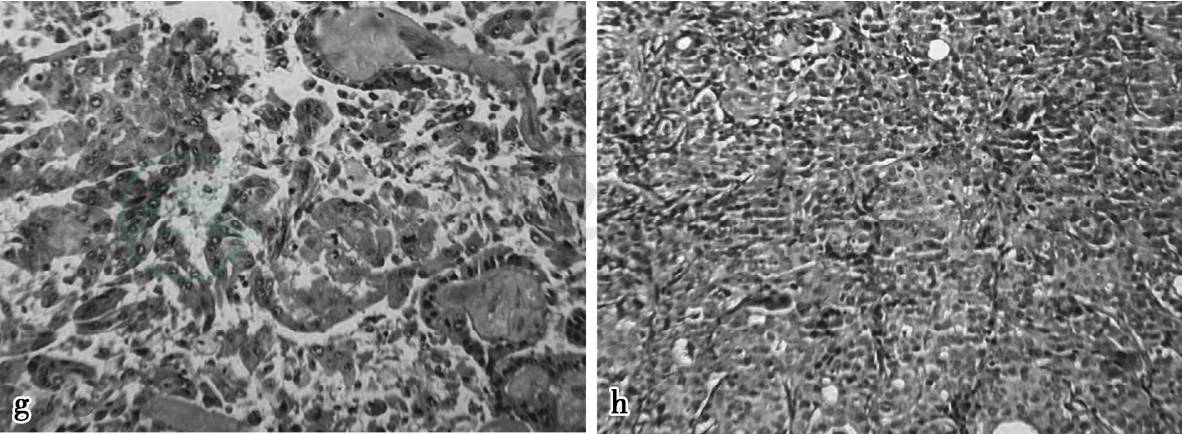

图2 g、h,病理结果为浸润性癌(见文后彩图)

诊断:病例2,浸润性癌,局部见脉管内癌栓

图19 c,病理示镜下可见导管上皮增生呈乳头状

图24 g、h,病理结果为浸润性癌